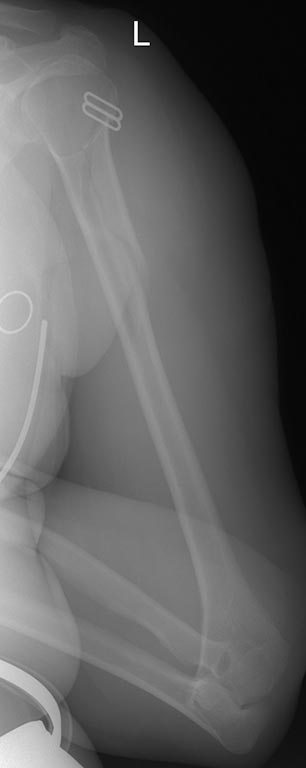

[Ortho] Нестабильность остеосинтеза, несращение перелома плечевой кости.

Еще Рентгенограммы

Имя     : 1.JPG